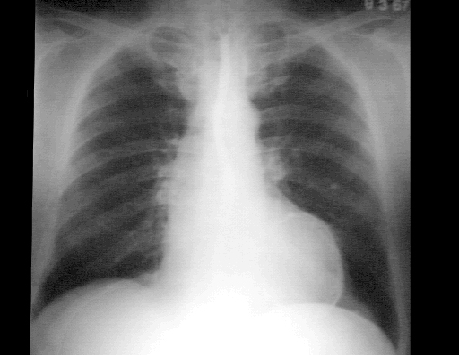

These chest X rays show a calcified left ventricular aneurysm.

This lateral chest X ray with barium swallow clearly shows the

circular density that defines a left ventricular aneurysm.